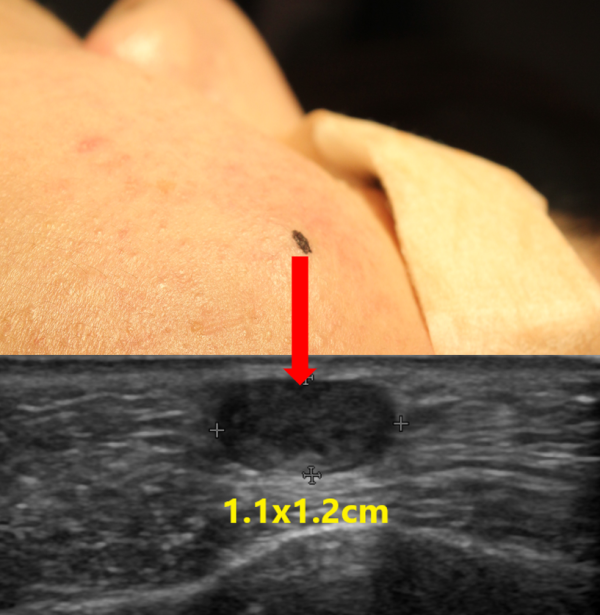

혹의 정확한 양상 및 크기, 피부로 부터의 깊이, 그리고 염증 소견이 있는지 확인하기 위해 초음파 검사를 시행하였습니다.

초음파상 가로x세로의 길이가 약 1.1x1.2cm 크기의 피지낭종으로 확인되었으며 피부로 부터 가까웠으며 염증소견은 없는 것으로 보였습니다.